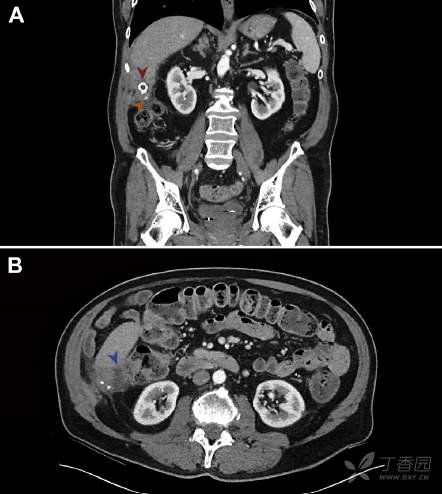

查体、血常规、血生化、大便培养无明显异常。粪钙卫蛋白8 mg/g (正常值 <49 mg/g)。腹盆腔CT检查所见如图A,图B。

请问:诊断是什么?

A 腹腔脓肿 B 肝脓肿波及结肠 C 放射性肠炎 D 结肠癌